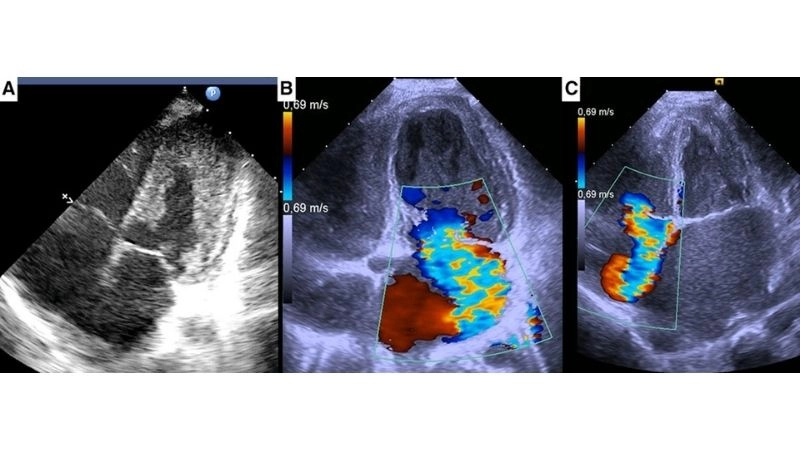

Images visual examples of eosinophilic myocarditis

Eosinophilic myocarditis is a rare inflammatory heart disease where eosinophils damage the cardiac muscle, causing weakness, chest pain, and sometimes severe complications like heart failure.